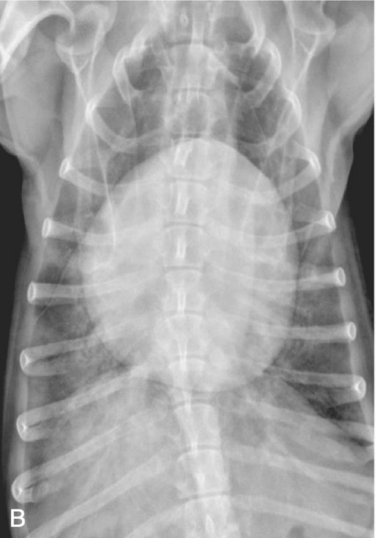

Bronchial signs

Tram line

Doughnuts

기관지벽 두꺼워질 때 보이는 sign

폐 말단으로 갈수록 깨끗한 게 정상

말단에도 tram line 보이면 비정상

VS.

(왼쪽이 정상, 말단으로 갈수록 깨끗. 말단에도 tram line 보이는 오른쪽은 비정상.)

흰색: doughnuts, 검은색: trams)